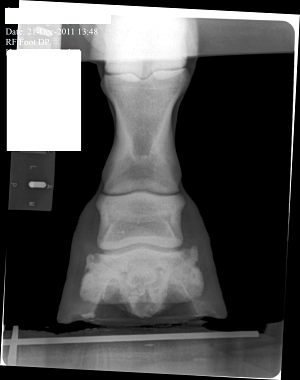

Posted on Friday, Jan 27, 2012 - 2:44 pm: The pastern joint doesn't appear to match the angle of the coffin joint or the fetlock joint...does it?What does this suggest? What else in these X-Rays would suggest 'trouble'? Mare is three and now in corrective shoes. Medial and Lateral balance was terrible. She is in a show barn and not worked a great deal and has little turn out. Thank you everyone.

Posted on Sunday, Jan 29, 2012 - 7:53 pm: Thanks Cheryl. It was late Friday when I posted, and I figured everyone would be off having a week end. Anyway, for what it's worth, I see the beginning possibly of side bone on the lateral side. I see the pastern joint angle does not match the angles of the fetlock and coffin joint. I cannot tell where the coffin joint is in relation to the coronary band. She has long under run heels and long toes. I don't know if the depth/shape of the collateral grooves tells me anything. The ski tip on the front of the coffin bone bothers me especially on a horse only 3. And is there a small bit or rotation down as well? I don't understand in the X-Ray why her sole appears to be bearing the weight and the hoof walls are off the ground. Is this really how she was prior to 'corrective' shoeing or is this X-Ray poorly taken or am I just poor at interpreting it. Or has her hoof mechanism sunk into the hoof capsule some? I do not have vet remarks for these X-Rays. |

Posted on Sunday, Jan 29, 2012 - 8:16 pm: left front The first X-Ray cut off the fetlock joint. This was not an editing error.The coffin joint looks uneven to me. Bigger space on the medial side. What does that mean? Nothing or something. I can't tell if this mare is built like a stack of playing cards or not(remember stacking cards like the wobbly Leaning tower of Pisa?). And how come the left lateral view the hoof wall is on the block but the right lateral view the hoof wall is off the block...is this an operator error or wonky foot? |

Posted on Tuesday, Jan 31, 2012 - 8:12 am: Hello Vicki,In general I avoid interpreting radiographs on the internet as the quality of the images here are not high enough to do a good job and the amount of time required to look at all aspects of the radiograph. I do invite members to put up radiographs and I will comment on any diagnosis made by the veterinarian who took the radiographs. That said I do think the RF foot in the front appears to have an overly long toe and corresponding toe flare and underrun heel. I don't see these issues in the L fore. The problem with assessing the conformational issues your bring forth is that technique and how the radiographs are taken can greatly effect the relationship between the bones and create false impressions. For instance all a horse has to do is stand a little forward over the foot and the normal pastern will not be aligned. The conformation issues you raise are best assessed looking that the horse while standing square and moving in a straight line than by a static set of radiographs. DrO |